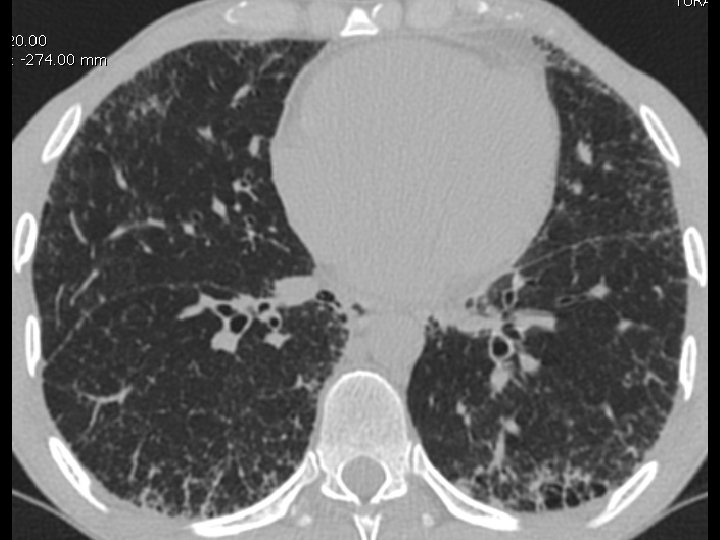

High-resolution CT scan

Subpleural, basal predominance Reticular abnormality Honeycombing with traction bronchiectasis UIPUIP Pattern

Subpleural, basal predominance Reticular abnormality Honeycombing with traction bronchiectasis Profuse micronodules UIPUIP Pattern Inconsistent with UIP Pattern

39 yo caucasian male, works in car collision repair and painting Multiple allergies, Gastroesophageal reflux disease and Thrombocytopenia of unknown etiology Smoker. No drugs CT: Reticular abnormality and honeycombing of subpleural basal predominance + micronodules Lung function tests: decreased diffusion capacity of the lung Blood tests: small increase of ESR and CRP; Autoimmune screening blood tests were normal BAL: normal celularity, with a mild increase in the neutrophil and eosinophil count

39 yo caucasian male, works in car collision repair and painting Multiple allergies, Gastroesophageal reflux disease and Thrombocytopenia of unknown etiology Smoker. No drugs CT: Reticular abnormality and honeycombing of subpleural basal predominance + micronodules Lung function tests: decreased diffusion capacity of the lung Blood tests: small increase of ESR and CRP; Autoimmune Screening Blood Tests were normal BAL: normal celularity, with a mild increase in the neutrophil and eosinophil count Definitive diagnosis can be established? Additional diagnostic tests required? Which tests?